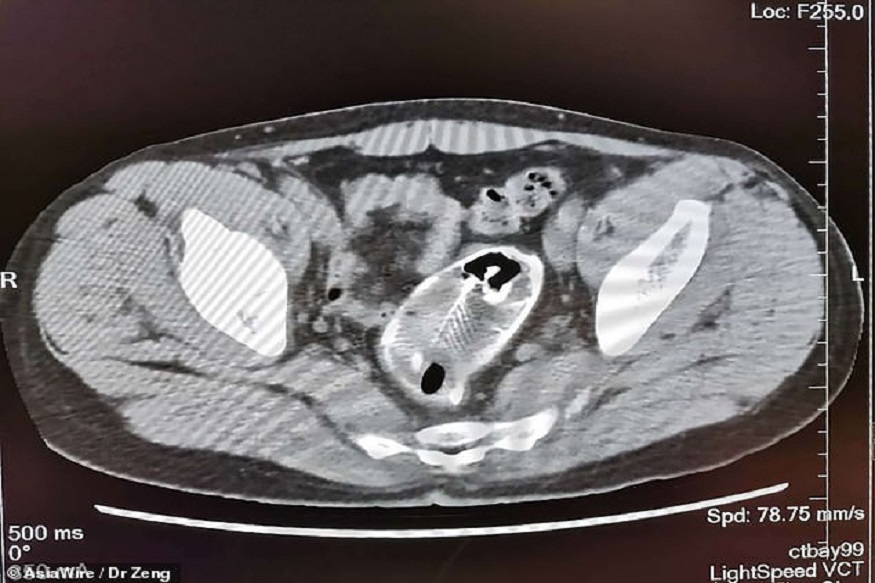

वाचा- चीनचा खोटारडेपणा आला समोर, कोरोना संसर्गाबाबत सगळ्यात मोठा रिसर्चनं केली पोलखोल एक्स-रेमध्ये दिसला मासा हा माणूस पोटदुखीची तक्रार घेऊन रुग्णालयात आला तेव्हा डॉक्टरांनी त्याला एक्स-रे काढण्याचा सल्ला दिला. त्यावेळी डॉक्टरांना रेक्टममध्ये काही तरी असल्याचा संशय आला. मात्र X-ray रिपोर्ट पाहून डॉक्टरांची झोप उडाली. या व्यक्तीची चौकशी करूनही त्यानं डॉक्टरांना काही माहिती दिली नाही. नंतर त्यानं कबूल केले की तो चुकून माशावर बसला आहे, म्हणूनच कदाचित तो त्याच्या गुदाशयात गेला आहे. त्यानंतर या व्यक्तीनं स्वत: मासा बाहेर काढण्याचा प्रयत्न केला होता, परंतु तसे होऊ शकले नाही. मग केलं ऑपरेशन हा मासा काढण्यासाठी डॉक्टरांना शस्त्रक्रिया करावी लागली. डॉक्टरांनी सांगितले की ही मासे गुदाशयात गेला होती, बरेच दिवस गेले होते आणि पुरेसा मोठा झाल्यामुळे ऑपरेशन केल्याशिवाय पर्याय नव्हता. डॉक्टरांनी सांगितले की मासे सडण्यास सुरवात झाली आहे, ज्यामुळे मलाशय आणि पोटात विष पसरू शकलं असतं. याआधी चीनमधील 68 वर्षांच्या व्यक्तीच्या गुदाशयातून 10 इंच लांबीचे दोन चॉपस्टिक देखील काढले गेले होते. वाचा- COVID19: 30 सेकंद हा Mouthwash वापरा आणि कोरोनाला गुडबाय करा!